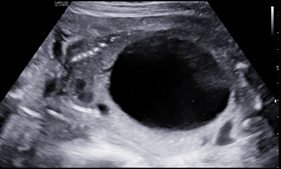

A 25-year-old G2P1001 at 19w2d presented for anatomic ultrasound. Routine prenatal genetic screening indicated an elevated risk for Down syndrome, 1:259. Her prenatal course was otherwise uncomplicated. Initial anatomical evaluation noted adequate amniotic fluid, a markedly distended fetal urinary bladder, moderate-to-marked bilateral renal hydronephrosis, a moderate degree of bilateral hydroureter, and bilateral renal cortical cysts, (Figures 1-4). Patient was sent for second opinion with secondary survey, within 1 week, denoting bladder outlet syndrome with oligohydramnios. A characteristic "keyhole" sign was noted (Figure 5). Patient initially elected for genetic non-invasive prenatal testing and later for genetic amniocentesis, the results of which revealed a normal karyotype/FISH/microarray. At the time of amniocentesis, bladder tap was performed and yielded 160cc of fluid for evaluation of renal function based on urine sodium, chloride, urine osmolality and calcium levels. At 22w3d patient presented for follow up sonographic evaluation; findings revealed significant fetal abdominal ascites, persistent oligohydramnios, a "bell-shaped" chest with only the left lung measurable, and the right lung poorly defined. Bilateral urinary tract dilation was again observed, with the right kidney measuring 2.0 x 3.0cm and the left kidney measuring 2.3 x 1.7cm. The kidneys were echogenic in nature and the parenchyma was thickened up to 7mm, with no pyramids visible. The bladder had severe thickening, measuring up to 7.7mm in diameter. The bladder measured 4.7 x 1.7cm with intraluminal calcifications noted both in the bladder and intestines. The patient was counseled on these new findings and concern for both pulmonary hypoplasia and possible poor renal function. The patient was given the option to proceed with fetal urinary evaluation for renal function and possible bladder shunt vs termination of pregnancy secondary to these findings; she elected for pregnancy termination.1–3

Figure 3 Moderate degree of bilateral hydroureter.

The presence of a posterior urethral valve prevents normal fetal micturition, resulting in bladder distension and subsequent distension of the ureters and kidneys. Diagnostic features of posterior urethral valves on sonography varies, but classically presents in male fetuses with fetal megacystis that may fill the entire abdomen, thickened bladder wall (>3mm) with prominent trabeculae, oligohydramnios, and bilateral hydronephrosis with hypoechoic renal parenchyma and/or cortical cysts that can indicate renal dysplasia. The best diagnostic clue is the presence of a dilated posterior urethra (“keyhole” sign) . While not always seen, its presence, suggests the diagnosis of PUV. These findings however, may be found in other urinary tract conditions. Megacystis is defined as a longitudinal bladder diameter (LBD) > 7mm in the first trimester. However, after the first trimester, it is most commonly defined as failure of bladder emptying during a 45min period of ultrasound examination.5